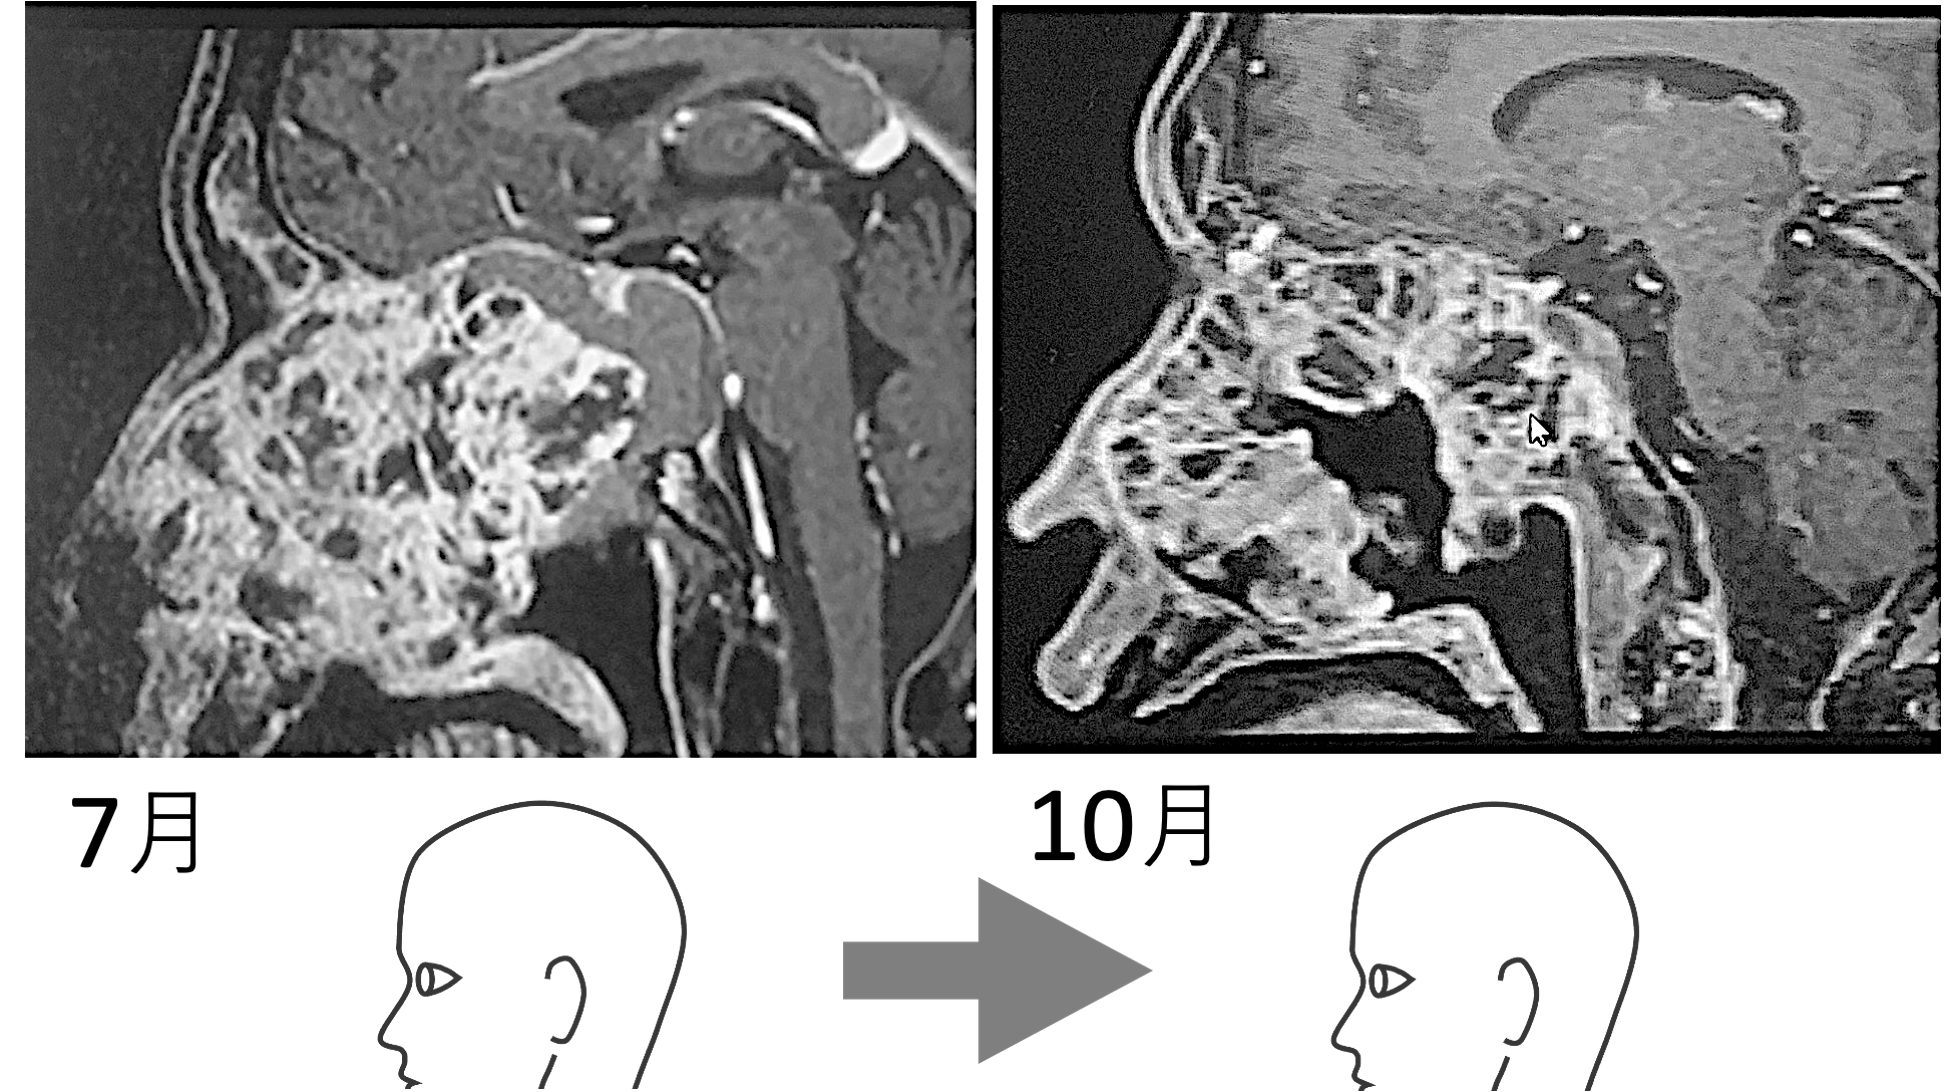

10月、画像診断でガンのコアに大きな空洞が映し出された。しかも巨大化しつつあるかに見えた全体像が縮小している。つまり真ん中に空洞ができては、その空洞が押しつぶされ小さくなり、それを繰り返しながら全体像が小さくなったのである。

下に置いた画像 (7月→10月) を見ていただくと分かるのだが、この血塊はガン中心部が崩れて排出されたものである。中心部が抜け落ちて、やがて少しずつガンの全体が縮小し、聴神経を圧迫しなくなったのである。ガン中心部から崩壊が始まったのだ。

ガン中心部が抜け落ちてできた空洞が、押されて小さくなっていくにつれて、ガン全体の輪郭も小さくなっていった。血塊が出ていないのに、7/20の血塊排出から時間を挟んで8/8に目が見えるようになった理由をそのように説明する。

すなわち、7/20血塊排出直後に画像を撮ったならば、その血塊分の空洞ができていたはずである。空洞ができ、ガンの圧力によって空洞が徐々に狭められるとともに、ガン全体のの輪郭が小さくなってきた。そう推測されるのである。

9/7〜8にかけて計7回のまとまった血塊排出があった。この直後で画像を撮っていれば、下画像 (10/20のMRI) よりも大きな空洞が写ったはずである。また大きなガンの輪郭が映し出されたはずである。ポッカリあいた空洞が押されて小さくなっていき、それにつれてガン全体の輪郭も小さくなっていくからである。

ガン中心部に空洞が出現した。あの血塊排出は、やはりガン排出だったのである。カチカチだったガンが、中心部からドロドロになり、ドロドロのガンを吐き出したのである。

画像でガンの中心部分が抜け落ちているとドクターから言われた。